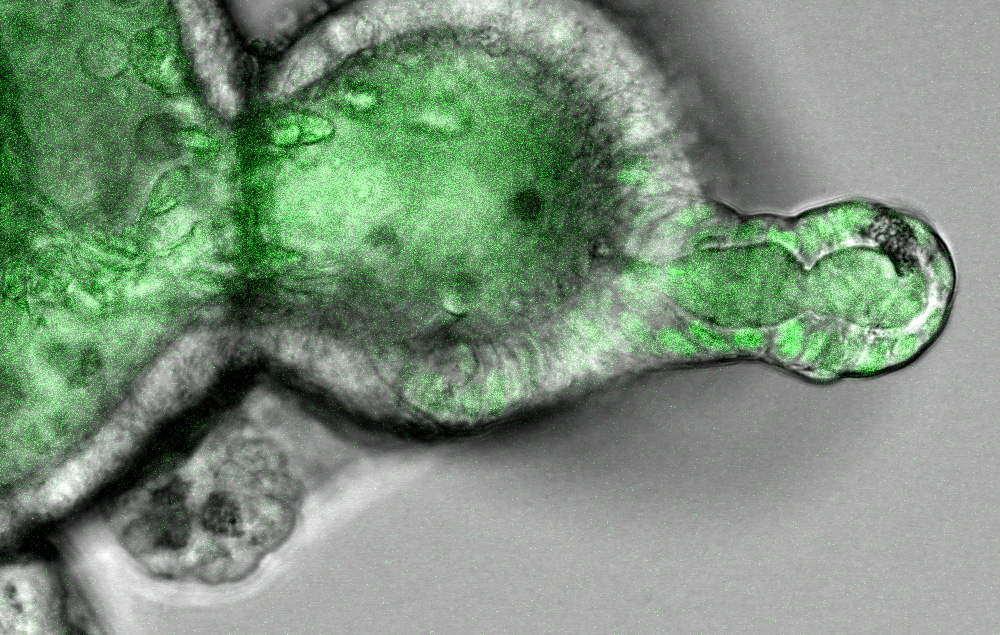

Ein Darm-Organoid wächst in einer dreidimensionalen Matrix und zeigt ein krebsauslösendes Wachstumssignal (ERK) als grüne Fluoreszenz im Zellkern. Die Zellkerne von Kryptenzellen (rechts) zeigen hohe Aktivität, während differenzierte Epithelzellen (links)

Beim Darmkrebs sind zwei Gene besonders häufig mutiert, die als KRAS und BRAF bezeichnet werden. Die genetischen Veränderungen in KRAS oder BRAF aktivieren in beiden Fällen denselben Signalweg. Als Reaktion auf diese Signale beginnen die Zellen, sich unkontrolliert zu teilen.

„Wir waren überrascht, dass Mutationen im KRAS-Gen beim Darmkrebs nur in einem Teil der Krebszellen eine Zellantwort auslösten, in anderen jedoch nicht. Der Unterschied scheint in der Zelldifferenzierung zu liegen, das heißt, im Bestreben der Krebszelle, zu einem bestimmten Zelltyp auszureifen. Das mutierte BRAF-Gen hingegen aktivierte die Wachstumssignale in allen Zellzuständen", fasst Morkel die wesentliche Entdeckung der Studie zusammen. Der KRAS- Signalweg spielt eine wichtige Rolle für die Zellteilung und ist daher ein zentraler Ansatzpunkt für die zielgerichtete Therapie von Darmkrebs.

Möglich machte diese Ergebnisse die Einzelzellanalyse. Mit deren Hilfe sind Wissenschaftler heute in der Lage, Unterschiede zwischen Tausenden einzelner Zellen eines Gewebes, wie z. B. des Darmgewebes, gezielt zu erforschen. Darüber hinaus nutzten Morkel und Kollegen die sogenannte Organoid-Technologie. Das Besondere daran: Aus Operationsmaterial gewonnene Zellen des Krebsgewebes wachsen im Labor zu dreidimensionalen Strukturen heran. Zusätzlich setzten die Forscher Computersimulationen ein, um zu verstehen, an welcher Stelle die Signalverarbeitung von der Zelle selbst blockiert werden kann. Die Krebszelle ist laut der Studienergebnisse in der Lage, die Informationskette für die unkontrollierte Zellteilung an bestimmten Punkten an- oder auszuschalten. Dies erklärt auch die häufige Beobachtung, dass bestimmte Signalwege innerhalb eines Darmtumors eben nicht in allen, sondern lediglich in einem Teil der Krebszellen aktiv sind – und das hat wiederum Auswirkungen auf die Behandelbarkeit der Tumoren.